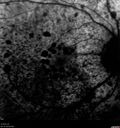

52 year old HIV negative man. May of 2014 the right eye had a vitrectomy for a floater. He was told that the doctor couldn't get all the floaters. He had cataract surgery (required 2 surgeries for the cataract). Them a different retina docotor then did another vitrectomy and scraped the scar tissue off the retina which had formed because the initial doctor couldn't get everything. The patient gave up a few months ago. He cannot see out of the right eye. There is constant flickering and distorted vision in the right eye. Since he stopped treatment his vision is no worse. He sees a fog out of the right eye and light and dark. 6/12/14 no pucker. The retina specialist who did the second vitrectomy also did laser to the macula to try to get rid of some of the swelling. The left eye is fine. The vision in the right eye is 20/63. There is diffuse chorioretinitis. There are no vitreous cells. With treatment of his neurosyphillis his vision improved from 20/63 to 20/32.

Syphilitic Chorioretinitis627 viewsSevere outer retinal atrophy and RPE non-geographic atrophy from syphilis. Vision improved from 20/63 to 20/32 with therapy. Images look a lot like DUSN. Patient had several surgeries (vitrectomy for floaters, vitrectomy for macular pucker, Avastin injections and macular laser for edema) prior by other retina specialists prior to being correctly diagnosed and treated.     (0 votes)